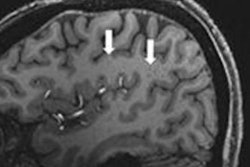

In a proof-of-concept study, a group led by Juan Eugenio Iglesias, PhD, of Massachusetts General Hospital in Boston trained a convolutional neural network (CNN) to synthesize images with 1-mm isotropic spatial resolution images from lower-resolution T1-weighted and T2-weighted brain images generated on a 0.064-tesla portable MRI scanner. In testing, the automated morphometry measurements on the synthetic images correlated highly with measurements on actual 1-mm isotopic images from high-field strength 1.5- to 3-tesla scanners.

In response, Iglesias et al developed LF-SynthS, a technique for training a CNN to generate synthetic images from low-field-strength image data. To test the model, they utilized automated segmentation tools on both the synthetic images and actual images acquired on high-field-strength systems in 24 patients who had presented with neurologic symptoms.

When the researchers compared the quantitative morphometric assessments on each type of image, they found high correlations between the synthetic images generated by the algorithm and actual high-field-strength images. Volumes correlated between synthetic image datasets based on low-field-strength MRI at 0.064 T and high-field-strength T1-weighted MPRAGE datasets for multiple brain regions, even for smaller regions that are difficult to segment (e.g., the hippocampus: r = 0.85; p < 0.001).